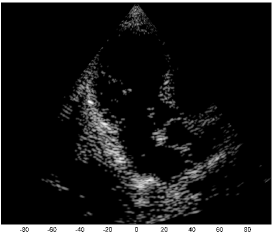

We examine the result of applying our scheme of Fig. 2 to raw RF data, acquired and stored for cardiac images of a healthy consenting volunteer. The acquisition was performed using a breadboard ultrasonic scanner of 64 acquisition channels. The transducer employed was a 64-element phased array probe, with central frequency, operating in second harmonic imaging mode: 3 half cycle pulses are transmitted at , resulting in a signal characterized by a rather narrow bandpass bandwidth, centered at . The corresponding second harmonic signal, centered at , is then acquired. The signal detected in each acquisition channel is amplified and digitized at a sampling-rate of . Data from all acquisition channels were acquired along 120 beams, forming a sector, where imaging to a depth of , we have . The results are illustrated in Fig. 3.

The first image (a) was generated using the standard technique, applying beamforming to data first sampled at the Nyquist rate, and then down-sampled, exploiting its limited essential bandwidth. For a single image line, sampling at , we acquire real-valued samples from each element, which are then down-sampled, to real-valued samples, used for beamforming. The resulting image is used as reference, which we aim at reproducing with our Xampling scheme. We begin by applying our scheme without approximation, simulating the modulation with the analog kernels defined in (11). Assuming reflectors, and using two-fold oversampling, comprises indices. Since each sample is complex, we get an eight-fold reduction in sample-rate. The resulting image (b) well depicts strong perturbations observed in (a). Isolated reflectors at the proximity of the array () remain well in focus. Applying our approximated scheme, for every , and , we choose and of (13) such that . At the current stage, this choice, and consequently the choice of and , are performed off-line, based on the imaging setup. This results in an average number of complex samples per receiving element, required for constructing each image line (with at most samples required for some combinations of and element indices). We arrive at a seven-fold reduction in sample rate, and the resulting image (c) appears very similar to (b).